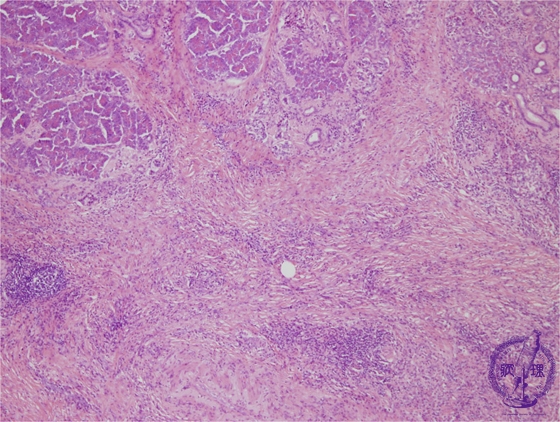

- (5)Chronic pancreatitis

Microscopic image(HE stain, low power): Advanced fibrosis is seen within the pancreatic parenchyma and interlobular spaces. Lymphoid follicles are seen forming amongst the fibrosis (arrows).